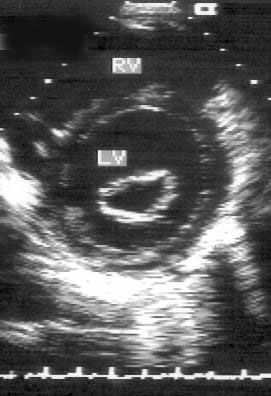

Парастернальная позиция короткой оси левого желудочка на уровне митрального клапана (рис. 2.9)

Из множества сечений левого желудочка, которые можно получить по его парастернальной короткой оси, выделяют позиции парастернальной короткой оси левого желудочка на уровне митрального клапана и на уровне папиллярных мышц. Эти позиции предназначены для исследования левого желудочка, правый желудочек может занимать относительно большое место на изображениях только при его дилатации. Иногда выделяются еще одну парастернальную позицию — по короткой оси левого желудочка на уровне верхушки, но на практике она используется редко.

Рисунок 2.9. Парастернальная позиция короткой оси левого желудочка на уровне митрального клапана. LV — левый желудочек, RV — правый желудочек.

Для получения парастернальной короткой оси левого желудочка на уровне митрального клапана датчик устанавливают слева от грудины в третьем, четвертом или пятом межреберье. Центральный ультразвуковой луч направляют перпендикулярно поверхности грудной клетки или слегка отклоняют влево. Датчик следует повернуть на 90° по отношению к плоскости, в которой регистрируют парастернальную длинную ось левого желудочка.

Ближе всего к датчику, т. е. в верхней части изображения оказывается часть правого желудочка. Структуры, относящиеся к трехстворчатому клапану часто видны в левой части изображения. В норме межжелудочковая перегородка своей выпуклостью обращена к правому желудочку. Левый желудочек, занимающий большую часть изображения, расположен правее и ниже и имеет округлую форму. Бывает непросто рассмотреть границу эндокарда левого желудочка в области его передне-медиальной и передне-латеральной стенок. В центре левого желудочка виден митральный клапан. Позиция парастернальной короткой оси левого желудочка на уровне митрального клапана получена правильно, если полость левого желудочка имеет округлую форму и хорошо видны передняя (выше на изображении) и задняя (ниже на изображении) створки митрального клапана.